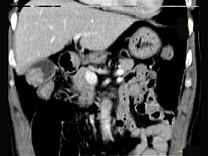

问题 男,45岁,右季肋区疼痛,Murphy征阳性,B超提示胆囊息肉,CT所见如图,最可能的诊断是 ( )

选项 A、胆囊转移癌 B、胆囊腺肌增生症 C、胆囊癌 D、慢性胆囊炎 E、胆囊息肉

答案 C